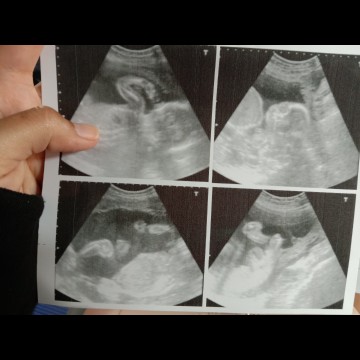

หมอบอกเพศญ.ดูตรงไหนหรอคะ

ดูแบบเดาๆ 😂 ก็ภาพข้างล่างใต้นิ้วมือแม่ค่ะ น้องยกเข่าชันขึ้นข้างหนึ่ง แล้วเห็นขีดๆ ตรงหว่างขาหน่อย และอีกภาพ ต่อจากภาพที่มีมือแม่ เห็นหน้าน้องชัด ภาพนี้จะดูจากข้างล่างขึ้นไปข้างบน ปล. ชอบภาพแรก ดูดนิ้วสนุกเลย 😁😁